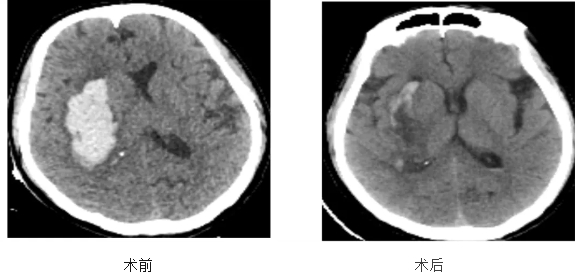

术后第一天患者意识清楚。复查头颅CT可见右侧基底节区脑内血肿已完全清除,脑组织及脑室受压解除,中线结构居中,颅骨缺损直径约1cm。经过两周的专业治疗,患者于9月2日顺利康复出院。